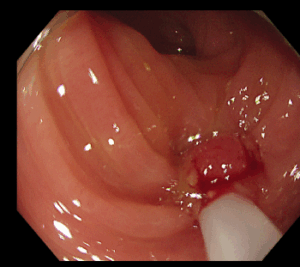

大腸内視鏡検査にてポリープを発見した場合、拡大観察を行い、そのポリープが将来がんになりやすいポリープかどうか判断します。その結果切除が必要と判断された場合には、可能な限り当日ポリープ切除を行います。ポリープが大きい場合、入院して切除が必要な場合、外科的に手術が必要な場合は無理して切除を行わず、安心して治療ができる大きな病院へ紹介する場合もあります。またポリープが多数ある場合は何回かに分けて切除することもあります。

当クリニックでは、ポリペクトミー(Hot、Cold)、EMR(粘膜切除術)を行っています。

*Coldポリペクトミー

小さなポリープはスネアと呼ばれる細いワイヤーで絞扼し切り取ります

*EMR

大きめのポリープや凹みのあるポリープは粘膜の下に局注を行い電気で焼灼して切り取ります。傷口はクリップと呼ばれる器具で塞ぎます。